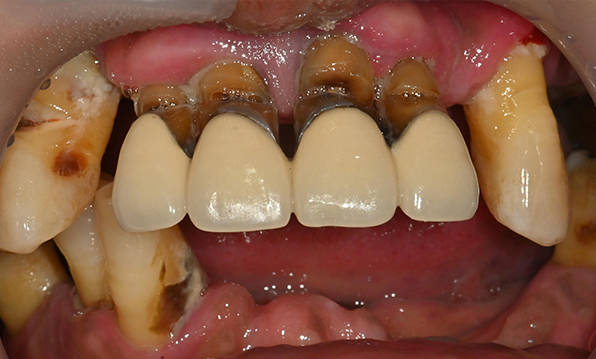

Before & After

| Before | After |